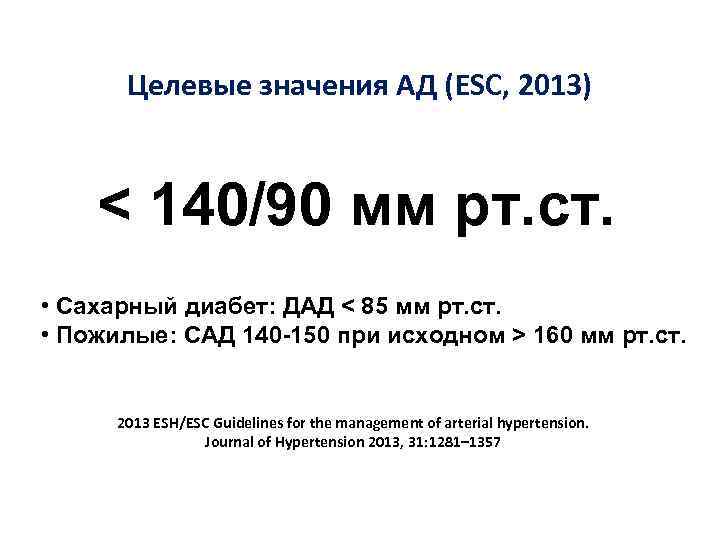

Целевые значения АД (ESC, 2013) < 140/90 мм рт. ст. • Сахарный диабет: ДАД < 85 мм рт. ст. • Пожилые: САД 140 -150 при исходном > 160 мм рт. ст. 2013 ESH/ESC Guidelines for the management of arterial hypertension. Journal of Hypertension 2013, 31: 1281– 1357

Целевые значения АД (ESC, 2013) < 140/90 мм рт. ст. • Сахарный диабет: ДАД < 85 мм рт. ст. • Пожилые: САД 140 -150 при исходном > 160 мм рт. ст. 2013 ESH/ESC Guidelines for the management of arterial hypertension. Journal of Hypertension 2013, 31: 1281– 1357